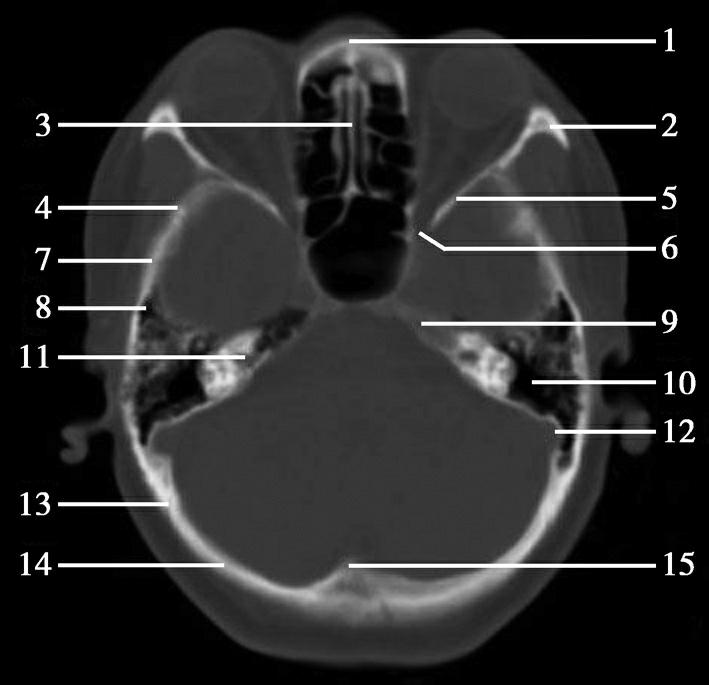

重要结构:卵圆孔、棘孔、破裂孔、斜坡、颞骨岩部、颈静脉孔(图1-2-1、图1-2-2)。

图1-2-1 颅底层面

A.横断面;B.横断面标注

1.晶状体;2.筛窦;3.颞肌;4.中颅窝底;5.外耳道;6.延髓;7.乙状窦;8.小脑半球;9.眼球;10.眼眶;11.上颌窦;12.蝶窦;13.乳突;14.耳郭;15.小脑蚓部;16.枕内隆凸

1.鼻骨;2.筛窦纸板;3.颧骨眶突;4.翼腭窝;5.蝶骨大翼;6.卵圆孔;7.破裂孔;8.颞骨颧突;9.棘孔;10.斜坡;11.颞骨岩部;12.乳突;13.颈静脉孔;14.枕乳突缝;15.枕骨;16.枕内隆凸

层面前部呈开口向前的“V”字形,正中为鼻中隔,向两侧依次为筛窦和眼眶,眼眶内前部为眼球,后部为眶脂体。翼腭窝位于眼眶后部,窝内含有脂肪并有上颌神经通过。层面中部为蝶骨体,蝶骨体中部可见含气蝶窦,蝶窦后方为枕骨基底部,两者呈前后关系,其上面构成斜坡。蝶窦两侧为蝶骨大翼,其后外侧缘处由前向后可见卵圆孔和棘孔,分别有下颌神经和脑膜中动脉通过。斜坡外侧、岩骨尖前方为破裂孔。蝶骨大翼与眶外侧壁的颧骨借颧弓相连,颧弓和蝶骨大翼之间有咬肌及颞肌。层面中部外侧为外耳道。颞骨岩部呈“八”字形,相互之间借破裂孔软骨、蝶岩软骨结合和岩枕软骨结合连接。岩部后外侧的乳突部内可见乳突小房,乳突部与枕骨相接。岩骨后部可见颈静脉孔,内有颈内静脉、舌咽神经、迷走神经和副神经通过。层面后部为颅后窝,其内可见延髓,延髓前方为延髓前池,内有椎动脉,后外侧为小脑半球下部,后方为第四脑室、小脑扁桃体及小脑蚓部。